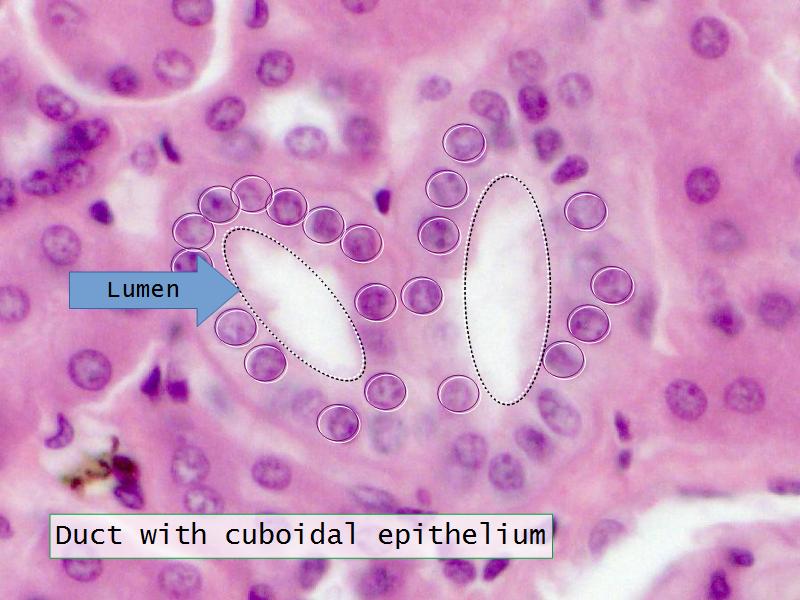

- Kidney = cuboidal, squamous

- Liver = squamous, cuboidal

Slides 28 & 76

Kidney: Objectives

- Basic arrangement of nephrons and collecting tubules in the kidney

- Structure of the nephron and collecting tubules

- Make an annotated diagram of a nephron, including the juxtaglomerular apparatus. Indicate the flow of blood and water in each part, and how solutes are filtered, secreted and reabsorbed.

- Complete the drawings for each slide in the practical workbook.